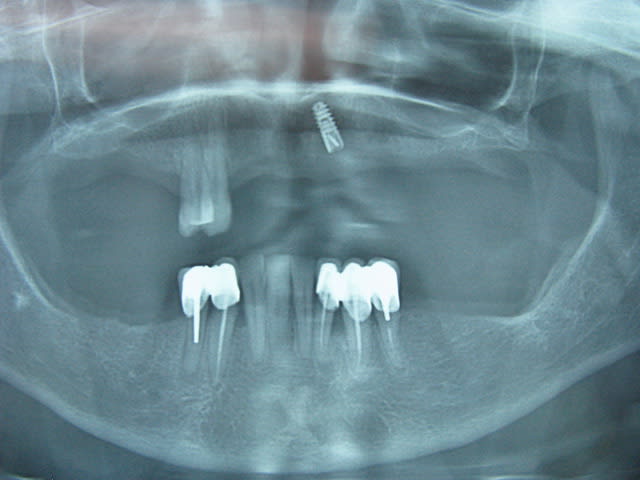

J'ai conclu par moi même qu'il fait de la merde en sur-équipant les patients , et récemment il fait de l'implanto . Voilà un superbe Not All on One , c'est un Ten On One . C'est beaaaaaauuu...)))

Img 3487 cuuqbi - Eugenol

Img 3488 h8ilol - Eugenol

Img 3489 cuhdog - Eugenol

Img 3491 pjrhic - Eugenol

Précision : Un correspondant et ami s'est chargé de l'extrimplantraction...car faut toujours avoir Dieu derrière soi pour combattre le diable devant les tribunaux . "Bin quoi ? Il était farpètement intégré mon implant , et dans le bon axe en plus !"